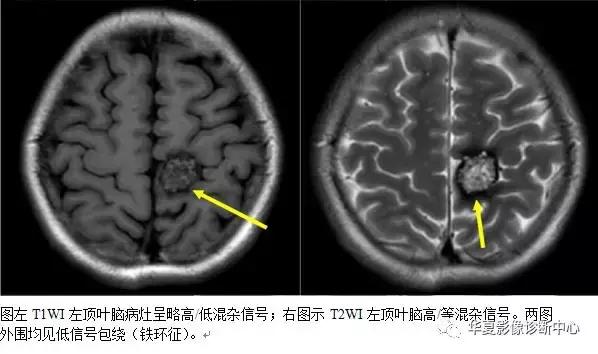

十七、铁环征:

由于反复多次少量慢性出血,多数颅内多数海绵状血管瘤周边可出现低信号环,有人将这种病灶周围低信号包绕形态称为“铁环征”,这是由于含铁血黄素沉着、单核细胞浸润和胶质增生等所致。多数病灶无明显占位效应。

MRI对脑海绵状血管瘤的诊断敏感性较CT高且具特异性,信号特征与其病理有关。T1WI像可呈低等混杂或略低信号,T2WI像呈高信号或混杂信号,表现为典型的“玉米花”样改变。脑海绵状血管瘤的信号随不同阶段的出血而表现不同,当脑海绵状血管瘤急性出血时,在T1WI上为等信号,在T2WI上为高信号,伴亚急性出血时,在T1WI、T2WI上均为高信号,由于反复多次少量慢性出血,多数脑海绵状血管瘤周边可出现环形低信号环,为含铁血黄素沉着、单核细胞浸润和胶质增生等所致,这是脑海绵状血管瘤的MRI特征性表现。其两大特征是:1)瘤灶中心的血栓和反复出血,内含游离稀释的正铁血红蛋白,在所有成像序列中均呈高信号;2)血栓与出血灶外周形成的含铁血黄素环在所有成像序列上都是黑色低信号,且T2WI像上最明显。有学者将其表现分为四型:I型,T1WI病灶核心呈高信号(含正铁血红蛋白),T2WI开始呈高信号,随后逐渐变低,病灶周围出现低信号圈,病理上相当于亚急性出血,由血肿边缘开始,正铁血红蛋白很快降解为含铁血黄素和铁蛋白;II型,T1WI病灶核心呈网状混杂信号,T2WI在网状混杂信号周围尚有一低信号圈,病理上相当于机化不一的血栓和小血肿;III型,T1WI呈等信号或低信号,T2WI明显高信号,病理上相当于慢性出血、血肿溶解后残留的含铁血黄素;IV型,T1WI与T2WI难以显示,梯度回拨序列成像呈许多针头大小的低或中等信号影像。尤其是梯度回波序列成像己被认为是诊断家族性脑海绵状血管瘤的“金标准”。

尽管脑海绵状血管瘤临床表现复杂,起病形式多样,但MRI有一定特征:1)病灶中的T1Wl显示低信号或等混杂信号,如有出血以高信号为主的混杂信号;2)T2 WI可见病灶周围含铁血黄素沉积,而出现“铁环征”;3)病灶周围常无或轻度脑组织水肿及占位效应不明;4)多数病灶不增强或轻微强化,5)高强场的MRI对脑海绵状血管瘤有较高的诊断特异性和敏感性。低信号环绕的桑甚状混杂信号团是脑内型海绵状血管瘤诊断的特异信号。